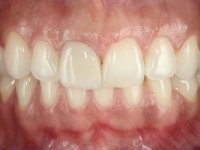

The patient was asked to remove the infiltrated crown and make a new crown with a ceramic-coated Zr infrastructure. As aesthetically, the crown was very well achieved, the patient and her dentist showed doubts about the need or not to intervene immediately. After clarifying my position on the infiltrated interfaces, we decided to jointly intervene. In these situations, the sooner you intervene the better

A pre-print was performed to make a crown in dual-cured resin. After a cross-section with a turbine, the infiltrated crown was removed with a microluxador. The dental stump was re-prepared to better define the shape and location of the cervical margin. It was necessary to place composite resin on the buccal surface of the provisional crown to improve its esthetics. The impression was made using a double-mix technique with two-viscosity, quick-setting silicones. In the laboratory, a crown with a ceramic-coated Zr infrastructure was made. After placing it in the mouth, we verified that the crown showed a greater translucency than the symmetrical one, not fulfilling our aesthetic goals. The ceramist had the opportunity to observe the situation in the clinic, collecting records for later rectification. The new crown was placed in the mouth and approved by the patient. The final cementation was done with resin-reinforced glass ionomer cement.